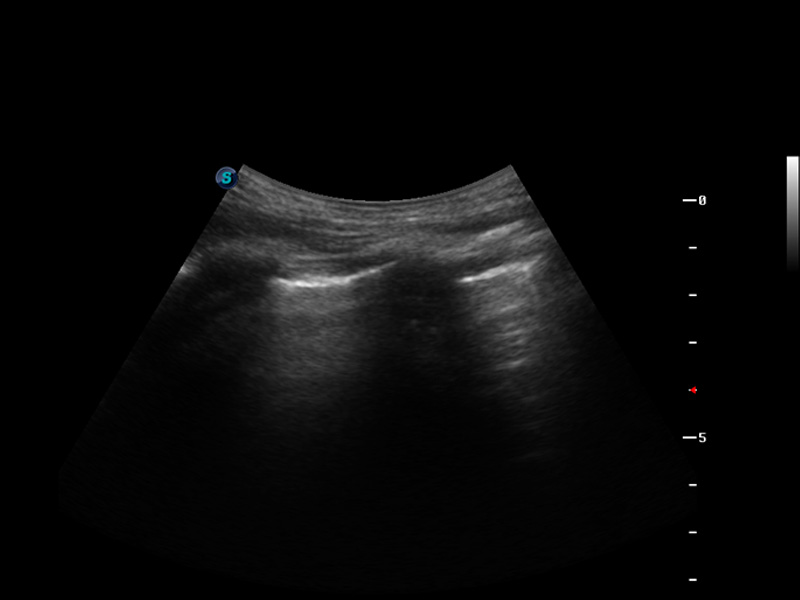

S9便携式彩色多普勒超声诊断仪是新葡的京集团8814检测站研发的高端便携彩超设备,外观设计新颖、产品性能卓越。S9在便携超声领域采用了突破传统的触摸屏交互设计,并以先进的软件硬件技术和设计理念,为您带来清晰的图像质量、稳定的工作性能和便捷的操作体验。

μ-Scan微米成像